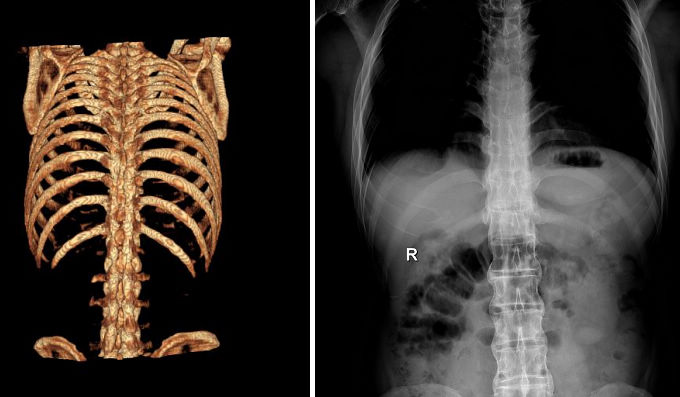

强直性脊柱炎

QZ16030094 姓名:陈先生 性别:男 年龄:32岁

- 病情

AS ①晚期 ②重度 病史:5年+

- 治疗

治疗后骶髂关节疼痛消失,腰椎前屈、背伸侧弯活动自如,膝关节无压痛感,复查血沉、C反应蛋白、等各项检查均已达到临床康复的标准。